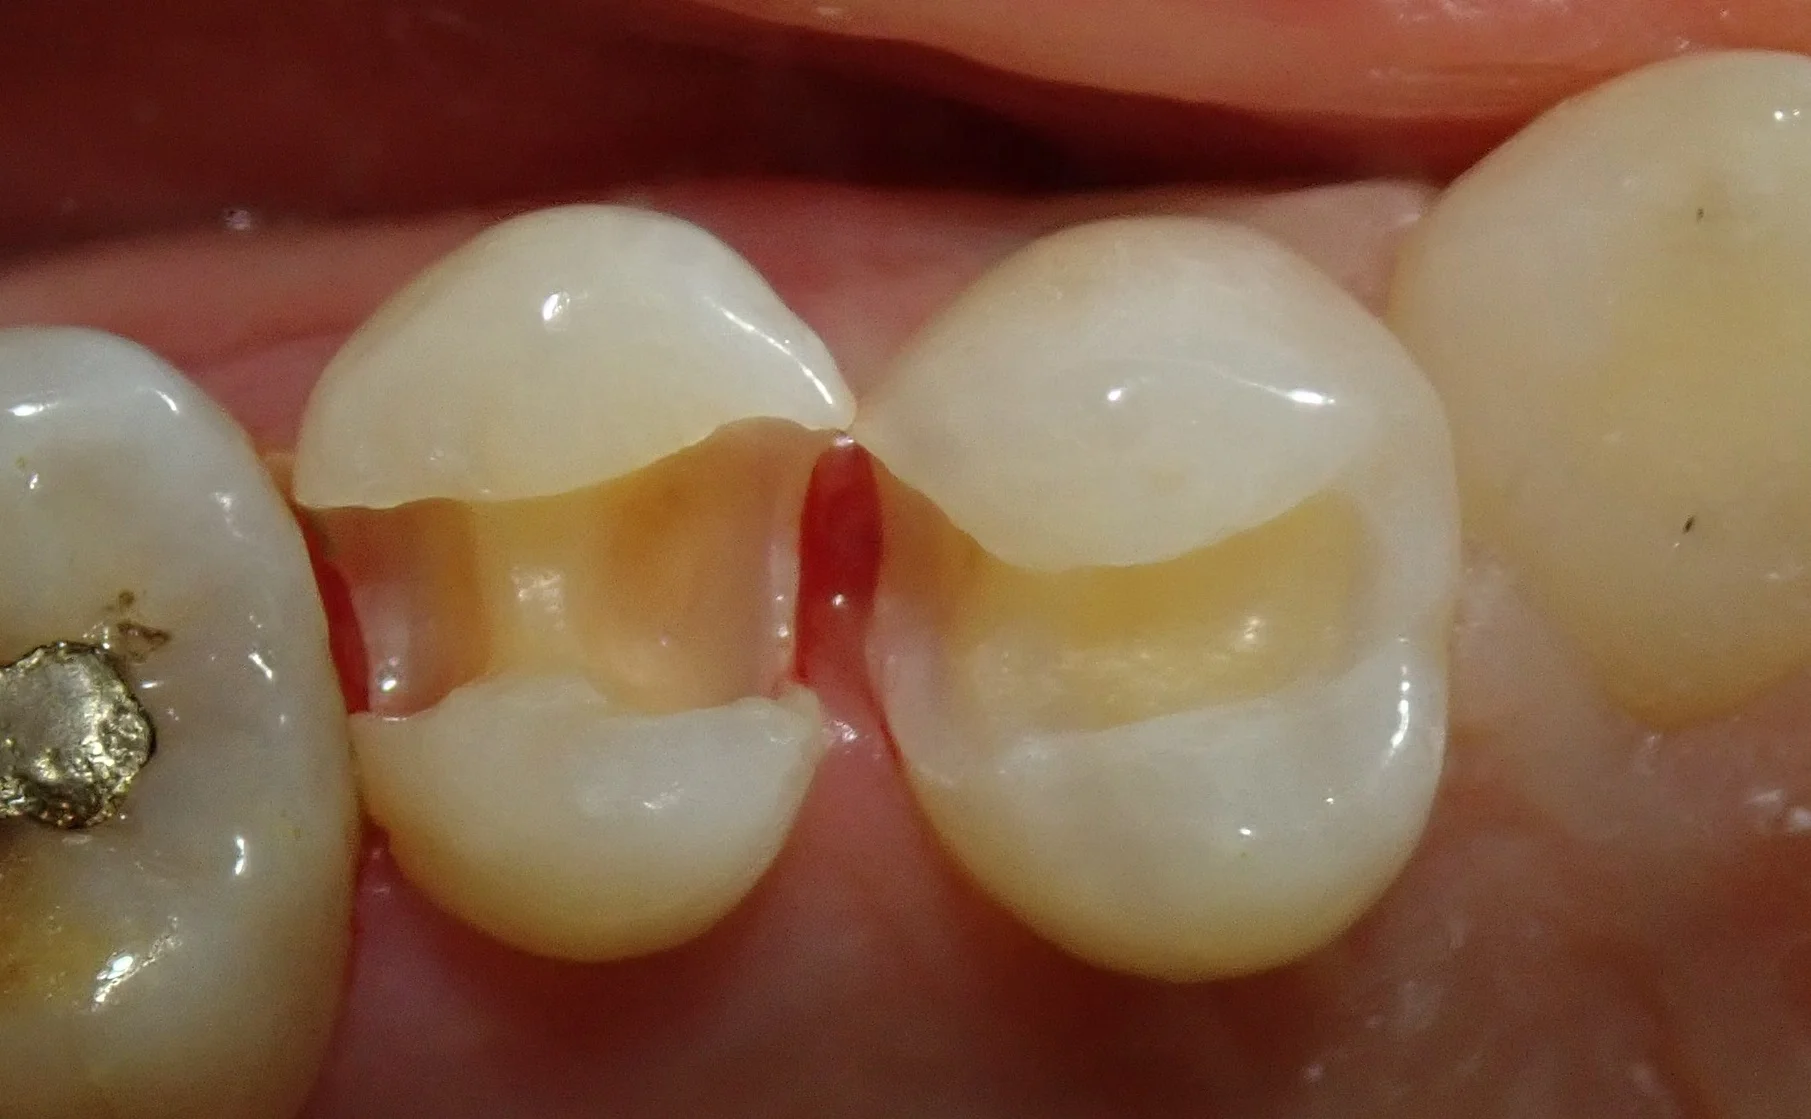

そして除去しきったのがこちら。

綺麗な色が露出したのがわかると思います。

左の虫歯については、歯の中央を超えて大きく進んでいましたね・・・。

結果として、リンゴの芯みたいな感じでしか、健康な部分が残りませんでした。